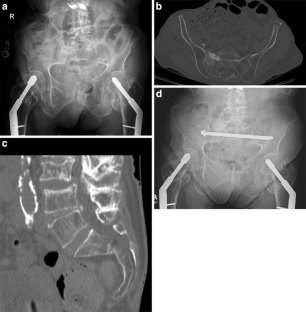

Fig. 1